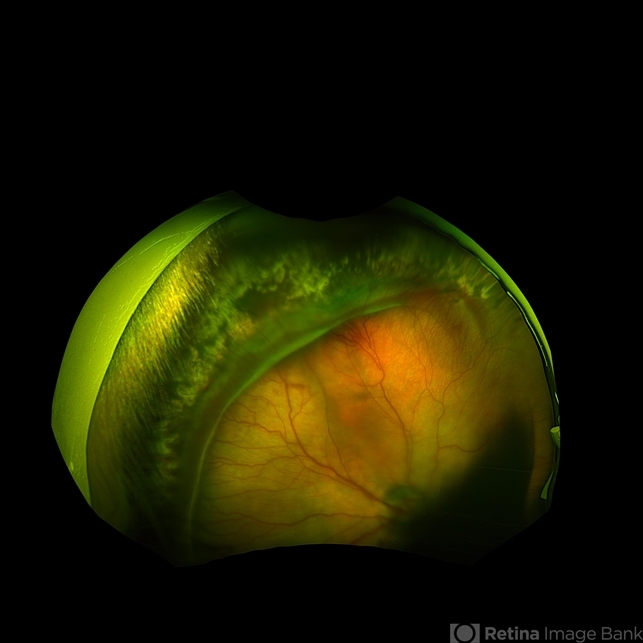

- retinopathy of prematurity stage 3, retinopathy of prematurity (ROP)

- Retinopathy of prematurity Stage 3 in a 5 month old baby. The flying baby technique was used to create this image.

- scanning laser ophthalmoscope